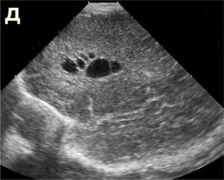

| Перивентрикулярный отек а, б, в, г - ребенок 2-х суток жизни с вдавленным переломом левой теменной кости. Структуры головного мозга симметричны. Сканирование во фронтальной и саггитальной плоскостях выявляет повышение эхогенности в перивентрикулярных областях без эхо-признаков других патологических изменений. При ДГ - невыраженное повышение показателей периферического сопротивления (спазм сосудов) д, е, ж - ребенок 1-х суток жизни от травматичных родов, парез Эрба слева, петехиальные кровоизлияния на лице, кровоизлияния в склеры, оценка по Apgar - 3-5 баллов. Определяется значительное повышение эхогенности в перивентрикулярной области, при ДГ - снижение показателей периферического сопротивления (парез сосудов). Перивентрикулярная лейкомаляция

|  |  | | а, б, в - фронтальные. |  |  | г, д - саггитальные сканы в разных плоскостях, В-режим. Определяются зоны перивентрикулярной лейкомаляции с обеих сторон. | Перивентрикулярное кровоизлияние в стадии псевдокисты